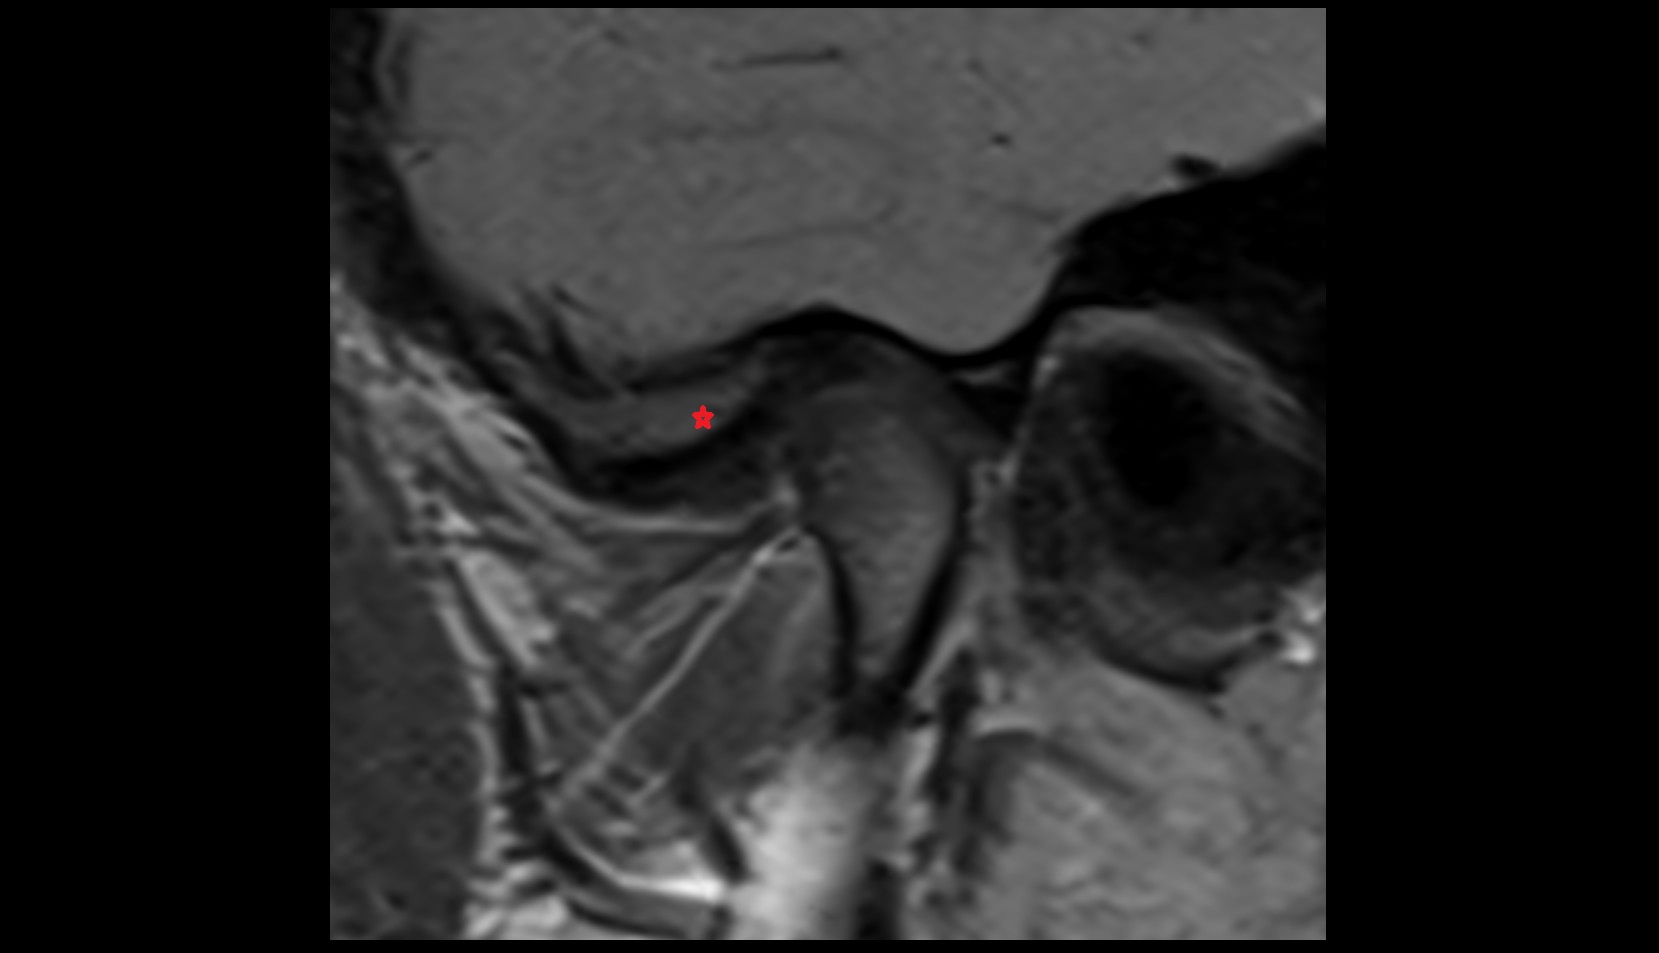

- Temporomandibular joint

- Articular disc of temporomandibular joint

- Articular eminence

- Mandibular condyle

- Mandibular fossa

- Superior head of lateral pterygoid muscle

- Inferior head of lateral pterygoid muscle